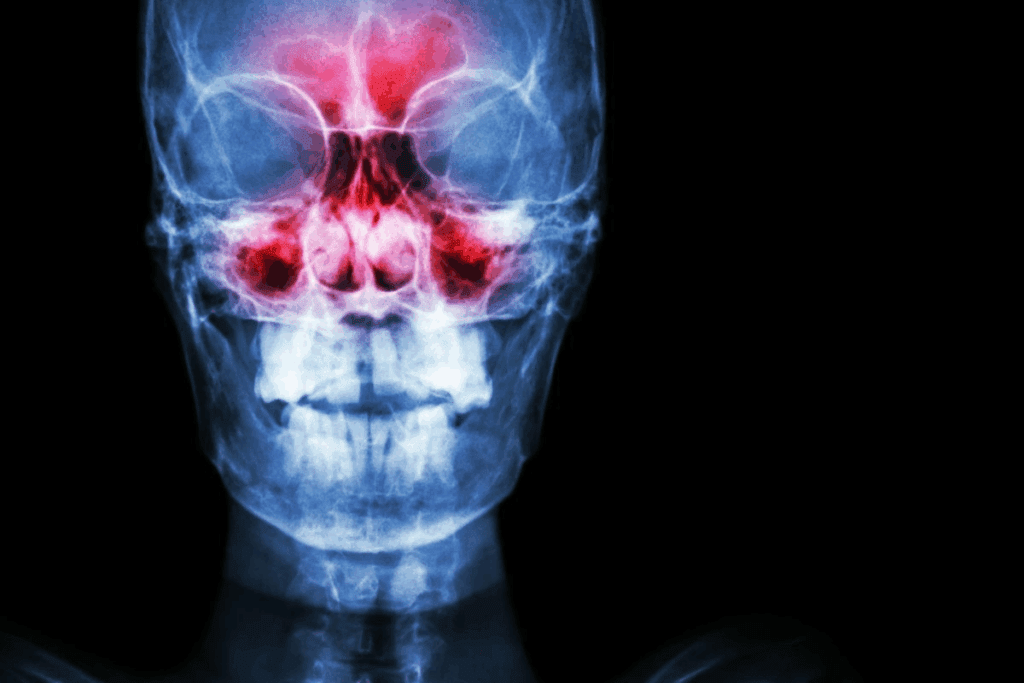

The sinuses are around the forehead, cheeks, and nose. They have a thin layer of mucus that keeps them moist. This mucus traps dust, bacteria, and other pathogens, stopping them from reaching the lungs. Knowing how healthy nasal mucous membranes work is key to understanding dry nasal passages.

Moisture balance is key for the sinuses to work right. If the nasal passages are too dry, the mucus becomes thick and sticky. This makes it hard to trap pathogens, leading to issues like:

- Increased risk of sinus infections

- Irritation and inflammation of the nasal passages

- Discomfort and pain in the sinuses

Risk of Dry Sinuses Infection

Dry sinuses are more likely to get infected. This is because the body’s natural defenses are weakened. Dry mucous membranes can’t trap pathogens well, making infections more common.